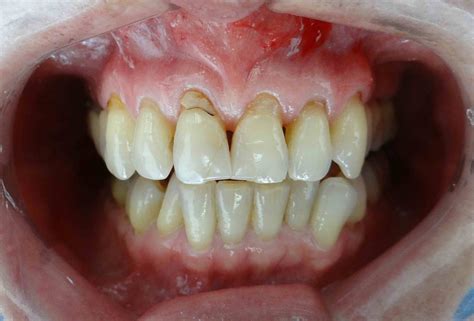

Cuando hablamos de encías retraídas nos referimos a un desplazamiento del tejido gingival que provoca una sobreexposición del diente. Las encías se desplazan hacia arriba en los dientes superiores y hacia abajo en los dientes inferiores dejando al descubierto parte de la raíz dental. Esto no solo afecta a la estética, sino que también compromete la protección natural de los dientes, aumentando la sensibilidad y el riesgo de enfermedades.

Hay diversas razones que pueden explicar la razón por la que tenemos encías retraídas. Entre las principales causas de encías retraídas destacan las enfermedades periodontales, como la periodontitis crónica y hábitos perjudiciales como un cepillado agresivo. Sin embargo, hay diversas razones que pueden explicar la razón por la que tenemos encías retraídas.

- Enfermedad periodontal: La gingivitis y la periodontitis son enfermedades que afectan las encías y los tejidos de soporte dental, contribuyendo a la recesión. También llamada periodontitis, esta enfermedad inflamatoria afecta a los tejidos que rodean el diente (periodonto). También conocida como piorrea, la periodontitis empieza como una gingivitis no tratada. Con el paso del tiempo, esta bolsa destruye el hueso y todo el tejido conjuntivo que rodea al diente.

- Cepillado agresivo o incorrecto: El uso de cepillos de cerdas duras y los movimientos bruscos pueden desgastar el tejido gingival. Seguramente la principal causa de retracción gingival sea el cepillado agresivo. El cepillado de nuestros dientes debe de ser suave sin hacer fuerza ni apretar.

Además de estas causas, existen factores predisponentes que incrementan el riesgo de retracción gingival. La genética juega un papel importante, ya que la encía del paciente puede ser genéticamente más o menos gruesa, siendo las encías gruesas más estables y las encías finas más inestables. En muchas ocasiones, y de forma natural, la raíz de los dientes no está rodeada de hueso en toda su superficie. Esto sucede sobre todo en la zona de los incisivos inferiores, donde el grosor de las raíces suele ser mayor a la anchura natural del hueso. También pasa a nivel de los caninos por la misma razón.